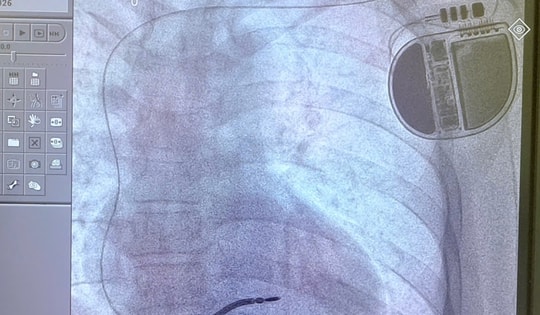

Phát triển kỹ thuật cao ở Bệnh viện Đa khoa An Giang, người dân không còn phải đi xa chữa bệnh

Những ca tạo nhịp tim và kỹ thuật TACE phức tạp được triển khai thành công, đánh dấu bước phát triển mạnh mẽ của Bệnh viện Đa khoa An Giang trong hành trình đưa kỹ thuật cao về gần dân.